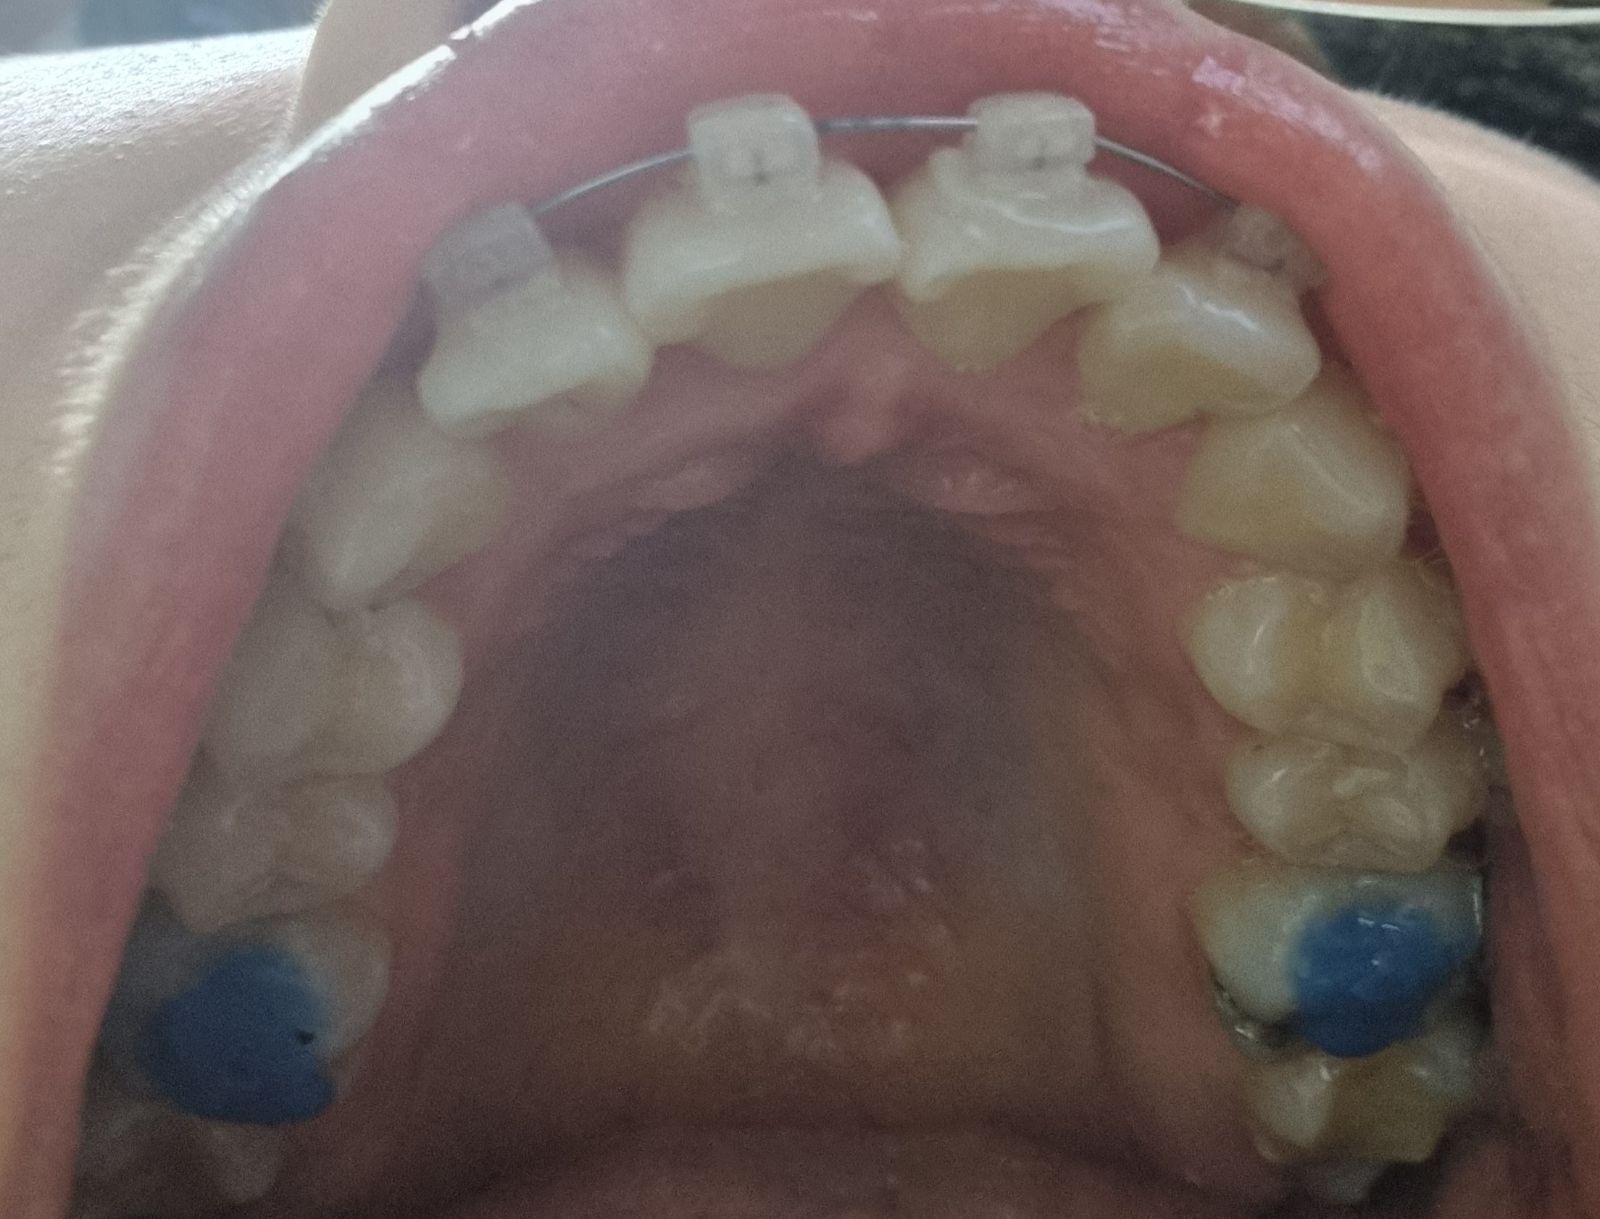

2022-03-06 2022-05-30 D+157 위의 사진은 3월달에 처음 바이트 블럭을 올렸을 때고

아래 사진은 지금 새로 올린 모습이에요.

확실히 저번보다 레진의 양이 많아졌네요.

왼쪽에 저 까만 점은 뭔지 모르겠는데

양치를 해도 손으로 긁어봐도 안없어 지네요..;;

바이트 블럭이 확실히 새로 올리니까

저작하는 느낌이 달라져서 그런지

불편한 느낌이 많이 왔습니다.